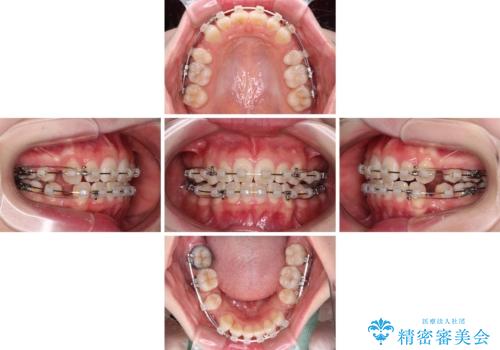

- 矯正装置

- クリアブラケット

- 治療期間

- 2年4ヶ月

- 前歯の出っ歯と口元の閉じにくさを気にして来院された患者様です。

口元を積極的に引っ込めるために、上下左右の小臼歯4本を抜歯することとしました。